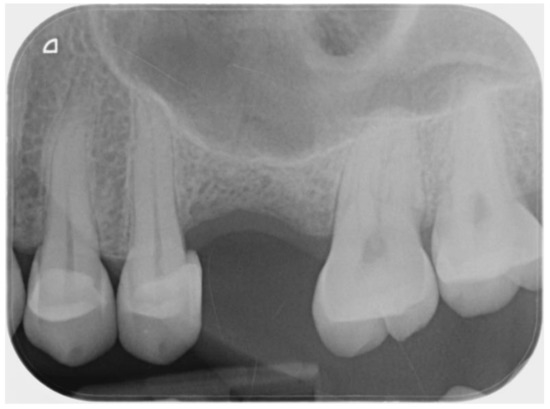

2.2. Surgical and Prosthetic Procedure

3. Results